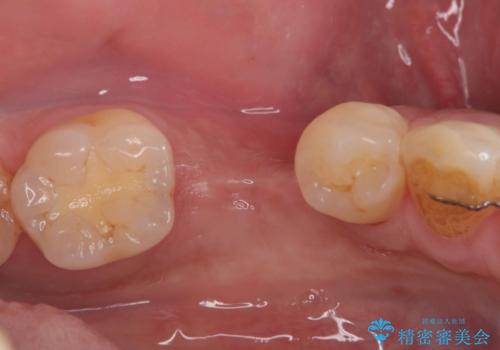

インプラントを抜去後、再びインプラントで治療を行いました。

20年以上振りのご来院でした。

なので、衛生士による定期的なクリーニングはとても大事です。